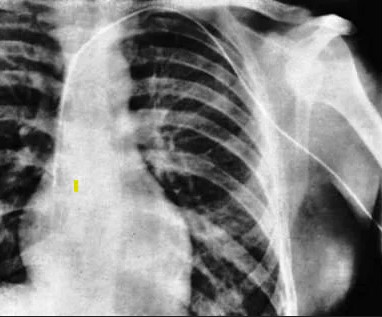

Es va fer ajudar el dia del cateterisme per una infermera, Gerda Ditzem, a qui va enredar perquè col·laborés. Forssmann es fa ell mateix una incisió a la vena cubital anterior del braç, per on introdueix un catèter urinari (Fig.2). Quan ja ha introduït 30 cm, se’n va caminant al Departament de Radiologia, que estava al soterrani de l’hospital, on convenç a un tècnic de que li faci una radiografia un cop ha introduït el catèter fins el cor. Werner no ha sentit cap dolor durant l’examen.

Ha demostrat que “el cateterisme és possible i no causa cap mal”. Escriu la seva experiència en un article curt que envia al Klinische Wochenscrift.